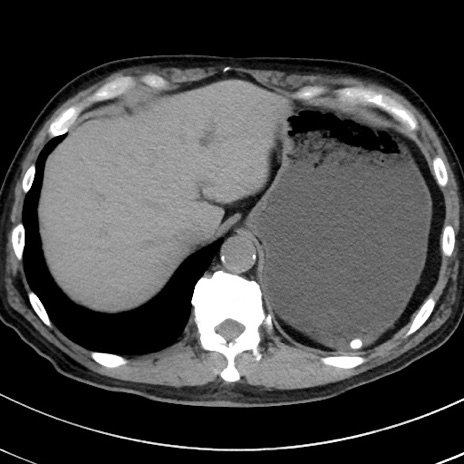

症例38(横断像)

【症例】70歳代 男性

【主訴】腹痛・嘔吐

【現病歴】昨晩より、嘔吐・腹痛あり。今朝になっても嘔吐あり。来院。

【既往歴】心臓バイパス手術、開腹胆摘、腸閉塞

【身体所見】BP 107/71mmHg、HR 116/min、腹部:平坦、軟、下腹部に軽度圧痛あり。反跳痛なし。

【データ】WBC 15100、CRP 0.32